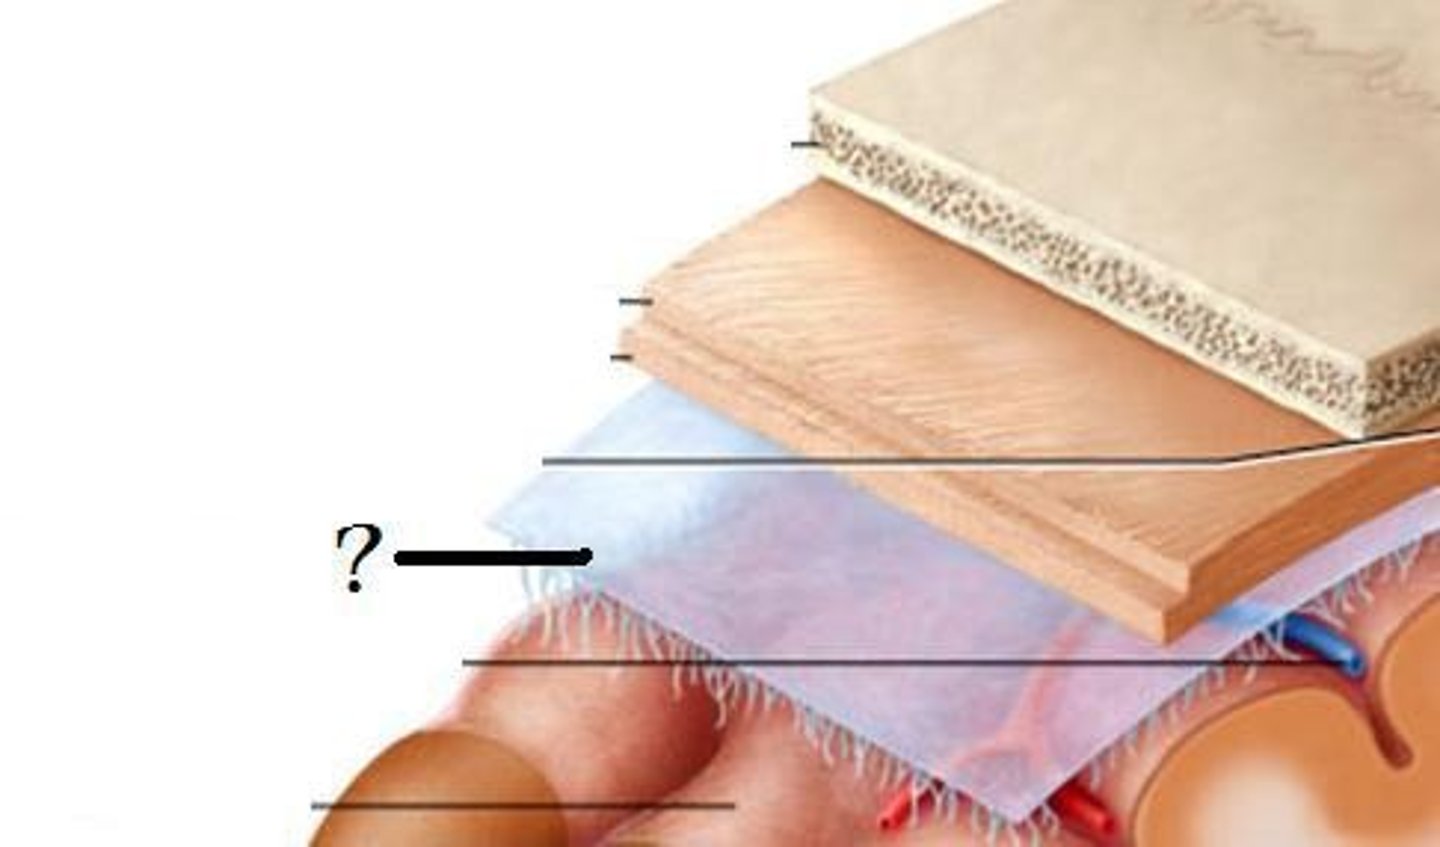

dura mater

periosteal layer

meningeal layer

arachnoid mater

subarachnoid space

with arachnoid trabeculae

pia mater